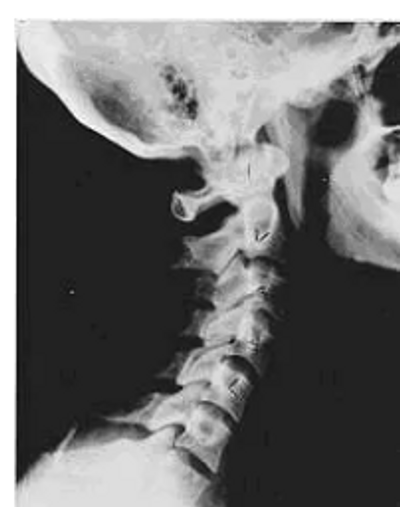

Phase Four Subluxation Degeneration

Phase four subluxation degeneration is seen with subluxations that have been ongoing, unchecked and uncorrected for over sixty five years. Phase four is a serious and grave condition that will negatively affect the patient’s longevity and quality of life. The massive amount of neurological damage caused by years of neglect that have lead to phase four degeneration are probably taking a serious toll on this person's health status. X-rays in phase four show serious severe structural changes. Vertebrae exhibit massive calcium changes, disc spaces appear blurred, and the bones themselves appear fused. It becomes extremely difficult to separate anatomical structures on x-ray. In this scenario the patient will have a severe restriction of range of motion in addition to probably a number of other health issues related to nervous system impingement. While reconstruction may not be possible in phase four degeneration, relief care can reduce symptoms which will improve the quality of life remaining. Patients in Phase Four Subluxation Degeneration have a serious situation structurally, functionally and neurologically, but they are certainly not beyond hope. Many patients in phase four report significant improvements in symptoms, conditions, mobility and quality of life with chiropractic care.